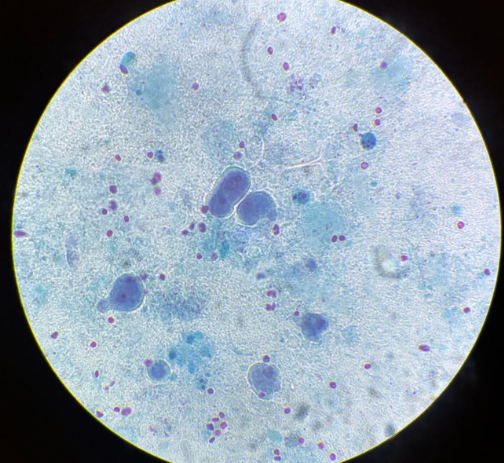

balantidium coli trofozoity